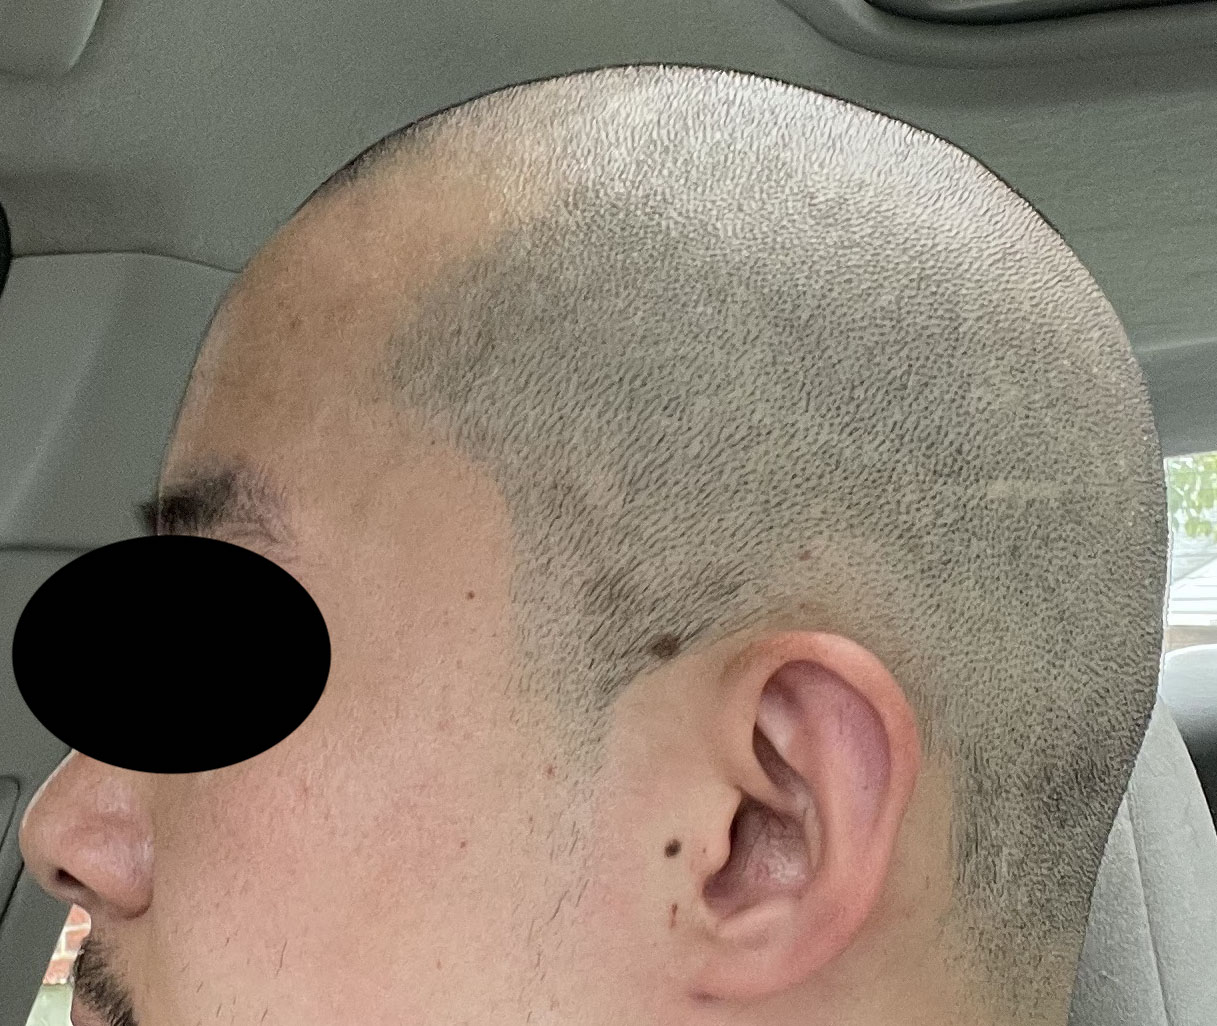

Patient 100

Desire for reshaping of an asymmetric flat back of the head in a shaved head male.

A combined back of the head reshaping procedure was done with a custom skull implant, sagittal ridge reduction and a right temporal muscle reduction.

Desire for reshaping of an asymmetric flat back of the head in a shaved head male.

A combined back of the head reshaping procedure was done with a custom skull implant, sagittal ridge reduction and a right temporal muscle reduction.